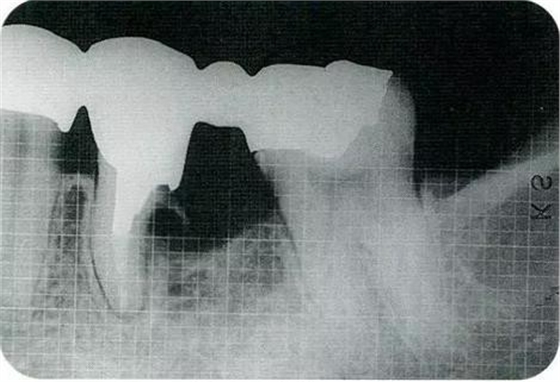

▼圖16-3

圖16-3對(duì)右上6.7顎側(cè)根的頰側(cè)牙槽中間骨脊缺失進(jìn)行處理,對(duì)應(yīng)高度來對(duì)右上5遠(yuǎn)中牙槽骨進(jìn)行少量切除。之后,對(duì)應(yīng)右上5遠(yuǎn)中牙槽骨的高度對(duì)近中以及右上4的牙槽骨進(jìn)行治療處理。牙槽骨的整體形態(tài)盡可能平坦,沒有極端的段差留下。之后,通過apically positioned flap進(jìn)行縫合固定。結(jié)果就能提高術(shù)后清潔性,得到良好的牙周環(huán)境。